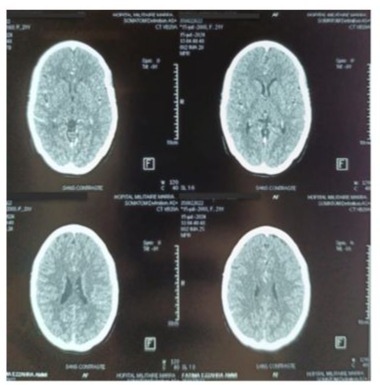

We present the clinical case of a 22-year-old female patient who underwent surgery for mitral stenosis complicated by atrial fibrillation and pulmonary hypertension. She received a mechanical valve and tricuspid valve repair. A year later, she experienced worsening symptoms. Examination revealed a thrombus on the mechanical valve. She was managed in the cardiac intensive care unit and received aspirin and heparin. Post-treatment, there was improvement in the transvalvular gradient and partial regression of the thrombus. She was discharged on acenocoumarin with regular monitoring. However, after one year (2 years post-surgery), she arrived at the emergency room with a more severe episode of acute global congestive heart failure. Upon clinical examination, crackles were detected in the lungs, along with mild hypoxia (O2 saturation 93%), and absence of fever or lower limb swelling. Blood pressure measured at 90/60 mmHg, with tachycardic atrial fibrillation (120 bpm) and a respiratory rate of 30/min. Chest X-ray revealed cardiomegaly and bilateral pulmonary edema. (Figure 1) Blood tests showed leukocytosis, elevated NT-proBNP levels (800), and moderate metabolic acidosis. Echocardiography documented near-complete blockage of the mechanical mitral valve leaflets with high transvalvular gradient and significant regurgitation. After initial stabilization with norepinephrine, heparin, diuretics, and dual antiplatelet therapy, her condition deteriorated on the fifth day with shock, hypoxia, and confusion, raising concerns about possible systemic embolisms, including secondary cerebral embolism, which was ruled out by a brain CT scan. (Figure 2) In a situation of mitral valve blood clot causing cardiogenic shock, norepinephrine dosage was increased to 15 mcg/kg/min and dobutamine started at 5 mcg/kg/min. TransThoracic Echocardiography (TTE)showed severe pulmonary hypertension, distended left atrium, high transvalvular gradient, severe mitral regurgitation, and hyperkinetic Left Ventricle (LV). Epinephrine was given, dobutamine stopped, and patient moved to operating room with equipment for perfusion and transfusion, and received vitamin K, exacyl, Vancomycin, and heating blanket.

Figure 2:Contrast brain CT scan in axial slices, performed to investigate delayed thromboembolic complications, returned without abnormalities.